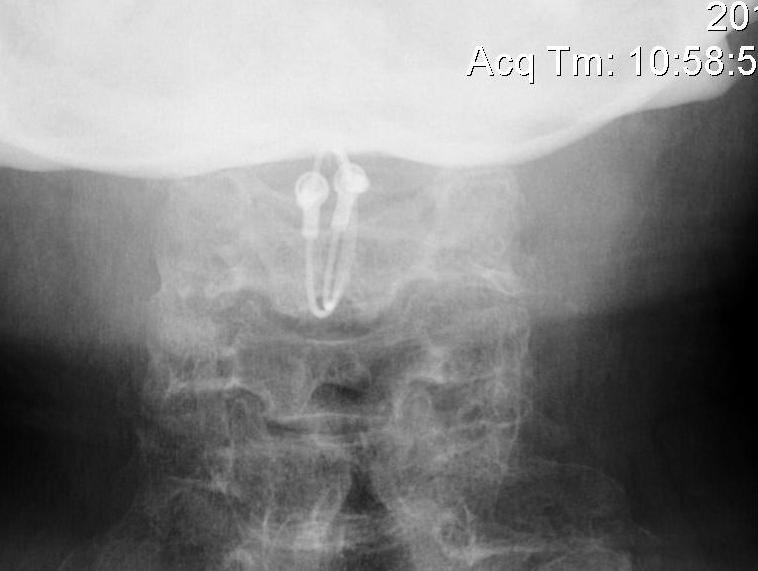

C1/C2 fusion

Options

1. Transarticular screws (Magerl)

2. C1 lateral mass / C2 pedicle screws (Goel-Harms)

+/- Brooks interlaminar wire with posterior bone graft

C1 lateral mass / C2 pedicle screws (Goel Harms)

Transarticular / Magerl screws from: Koepke et al Nature Reports

Results

Ryu et al World Neurosurg 2017

- 58 patients with RA and AAS

- treated with either transarticular screws or C1/C2 screws

- no difference in fusion rates / clinical outcomes / complications